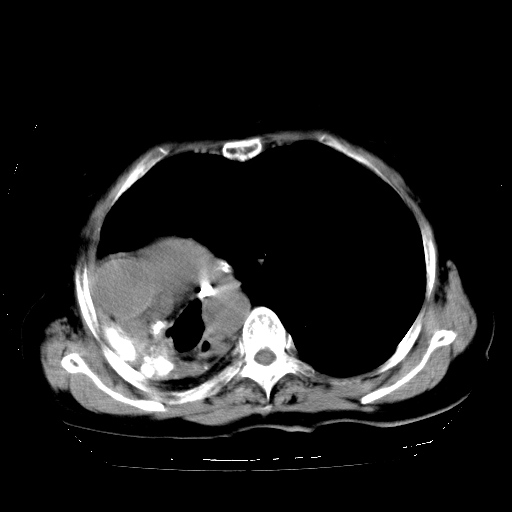

标题: CT23991:女,72岁,咳嗽、憋气一周。 [打印本页]

女,72岁,咳嗽、憋气一周,十年前曾患肺结核及胸膜结核。

右侧毁损肺,右侧纵隔疝

右侧毁损肺,右侧纵隔疝,左肺代偿!

1.右侧损毁肺伴胸膜钙化,2.左肺小结节灶,良性可能大,注意复查。3.肝脏左叶囊肿。4.先天性一侧肺不发育待出外(右侧胸廓无明显塌陷)。对比原片应该非常有帮助。